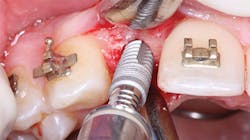

Figure 4: On screwing the implant into place, bone density or lack of it is obvious.

These above suggestions are some of the same criteria that guide the implant-placing dentist who gives you loading suggestions. However, if you are not placing the implants, you do not have the opportunity to evaluate the bone condition at the time of implant placement (figures 3 and 4). The following topics are a few factors or techniques that can help you decide when to load the implant: